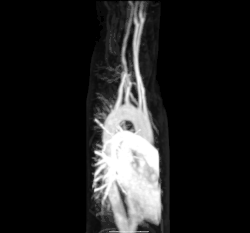

Кровеносная система человека. Красным обозначены артерии, синим — вены. Капиляры соединяют артерии с венами. | |

Циркулято́рная система, также система кровообращения и кровеносная система[1] — система органов, включающая сердце, кровеносные сосуды и кровь, которая циркулирует по всему телу человека или другого позвоночного[2][3]. Включает в себя сердечно-сосудистую систему (также кардио-васкулярная система от греческого kardia — сердце, и латинского vascula — сосуды), которая состоит из сердца и кровеносных сосудов. Кровеносная система состоит из большого и малого круга кровообращения[4].

Система кровообращения включает сердце, кровеносные сосуды и кровь[3]. Сердечно-сосудистая система у всех позвоночных состоит из сердца и сосудов. Кровеносная система делится на два основных контура — малый и большой круги кровообращения[2][4]. Малый круг кровообращения представляет собой контурную петлю от правого желудочка, по которой кровь поступает в легкие, где она насыщается кислородом и возвращается в левый желудочек. Большой круг кровообращения доставляет насыщенную кислородом кровь от левого желудочка к остальной части тела и возвращает кровь обратно в правый желудочек через крупные вены, известные как полые вены. Циркуляцию крови также можно разделить на две части — макроциркуляцию и микроциркуляцию. В среднем у взрослого человека содержится от пяти до шести литров крови, что составляет примерно 7 % от общей массы тела[9]. Кровь состоит из плазмы, эритроцитов, лейкоцитов и тромбоцитов . Пищеварительная система также работает совместно с системой кровообращения, обеспечивая организм питательными веществами, необходимыми для поддержания работы сердца[10].

К кровеносным сосудам относятся артерии, вены и капилляры. Крупные артерии и вены, несущие кровь к сердцу и от него, известны как крупные сосуды[14].

Насыщенная кислородом кровь поступает в большой круг кровообращения при выходе из левого желудочка через аортальный клапан[15]. Первой частью большого круга кровообращения является аорта, массивная и толстостенная артерия. Аорта изгибается и разветвляется, снабжая кровью верхнюю часть тела, пройдя через аортальное отверстие диафрагмы на уровне десятого грудного позвонка, входит в брюшную полость[16]. Затем ветви аорты спускаются в живот, таз, промежность и нижние конечности[17] .